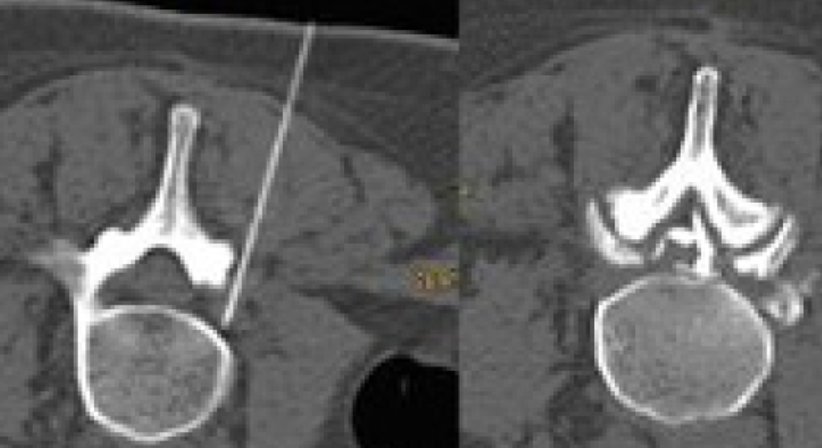

Die interventionell-radiologische Schmerztherapie ist ein effektives minimal-invasives Verfahren, das je nach Schmerzursache in 80-90% zu einer Schmerzlinderung führt. Unser Spezialgebiet ist die Behandlung chronischer Rückenschmerzen.